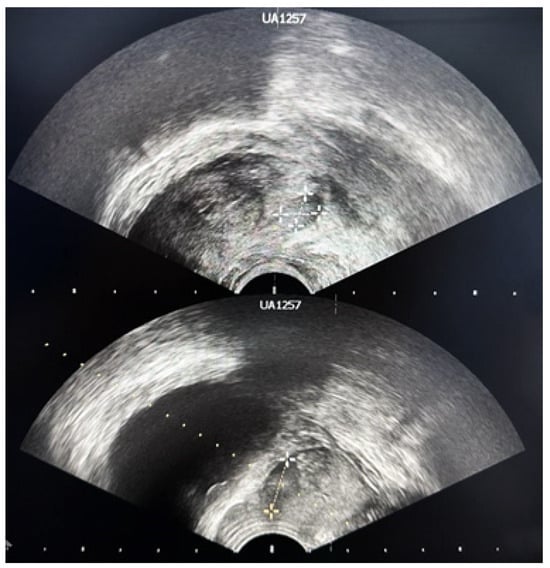

4. Transrectal Ultrasound (TRUS)-Guided Prostate Biopsy

6. Technical Difficulties

6.4. Location of the Suspicious Lesion

6.5. Prostate Motion